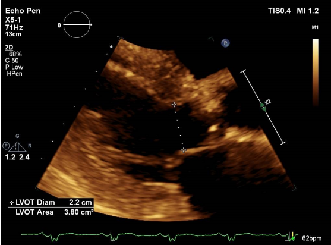

心脏彩超提示:

超声诊断:主动脉瓣重度狭窄;轻度二尖瓣反流,轻度三尖瓣反流;轻度肺动脉高压。

STS分数4.132%。NT-proBNP 837 pg/L(0-125);TNT 369 ng/mL (ULN<100);CREA 79.4 umol/L;LVEF 55%;BP:132/75 mmHg。